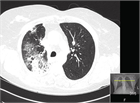

1. 放射線照射開始後早期に発症した放射線肺臓炎は重症化しやすい。

1. 放射線治療によって器質化肺炎(OP、BOOP)が起こることがある。

1. 高精度放射線治療においても放射線肺炎の発症頻度は低くはない。